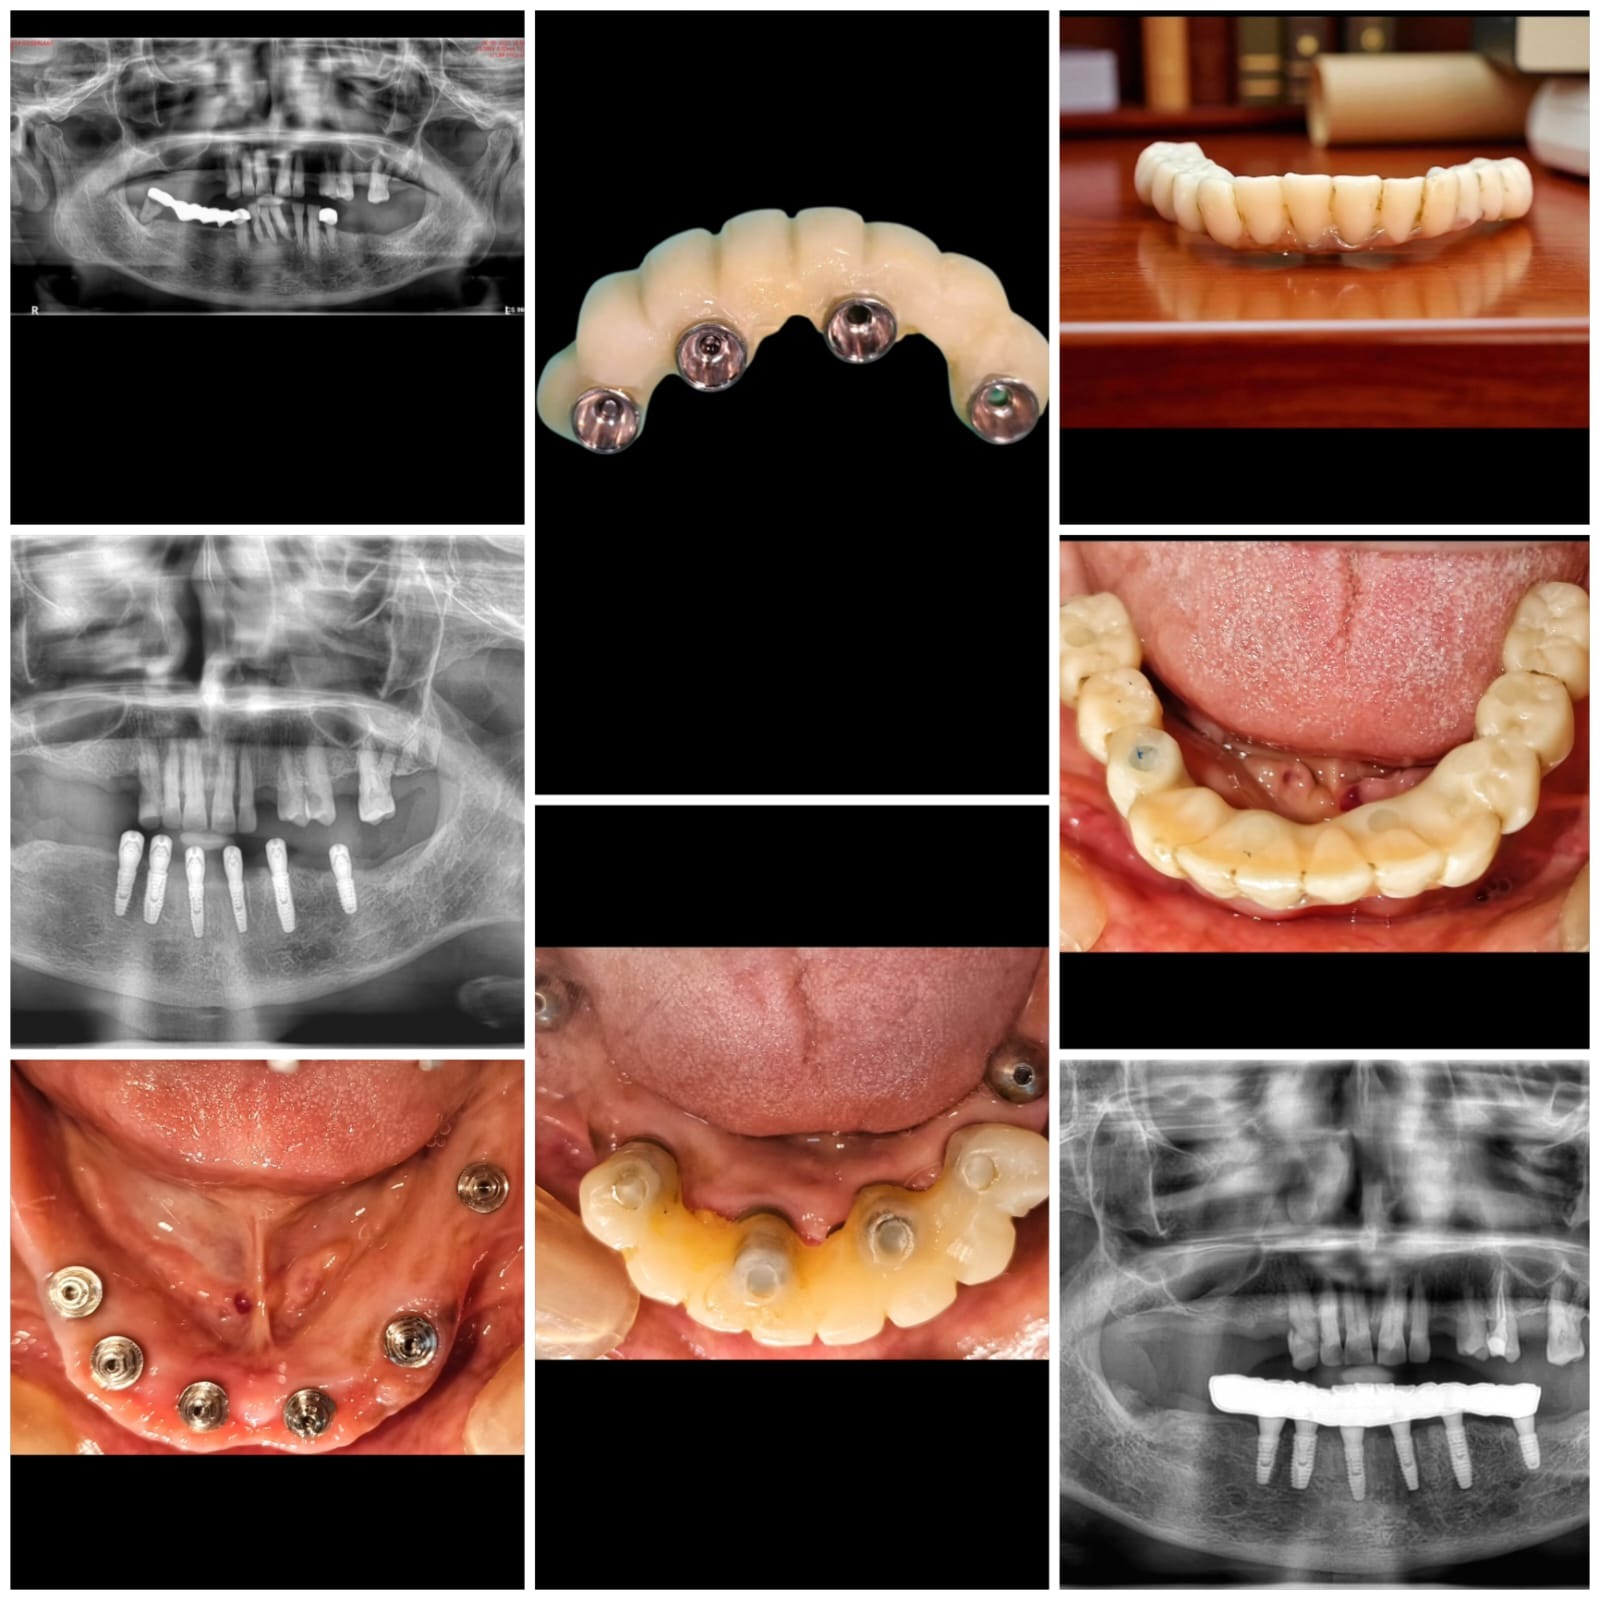

FULL ARCH IMPLANT REHABILITATION IMMEDIATE PLACEMENT & LOADING.

FROM HOPLESS DENTITION TO A CONFIDENT NEW SMILE JUST IN 3 MONTHS AT 'PROCARE DENTAL THANE' !!

USING NEOBIOTECH IMPLANTS WE ACHIEVED:

1. IMMEDIATE EXTRACTION AND IMPLANT PLACEMENT

2. IMMEDIATE LOADING WITH A PROVISIONAL PROSTHESIS

3. FINAL PROSTHESIS DELIVERED AFTER 3 MONTHS WITH EXCELLENT STABILITY & ESTHETICS.

THIS CASE HIGHLIGHTS HOW DIGITAL PLANNING + ADVANCED IMPLANT SYSTEMS MAKE IT POSSIBLE TO RESTORE FUNCTION, ESTHETICS, & CONFIDENCE IN A SHORT SPAN OF TIME.